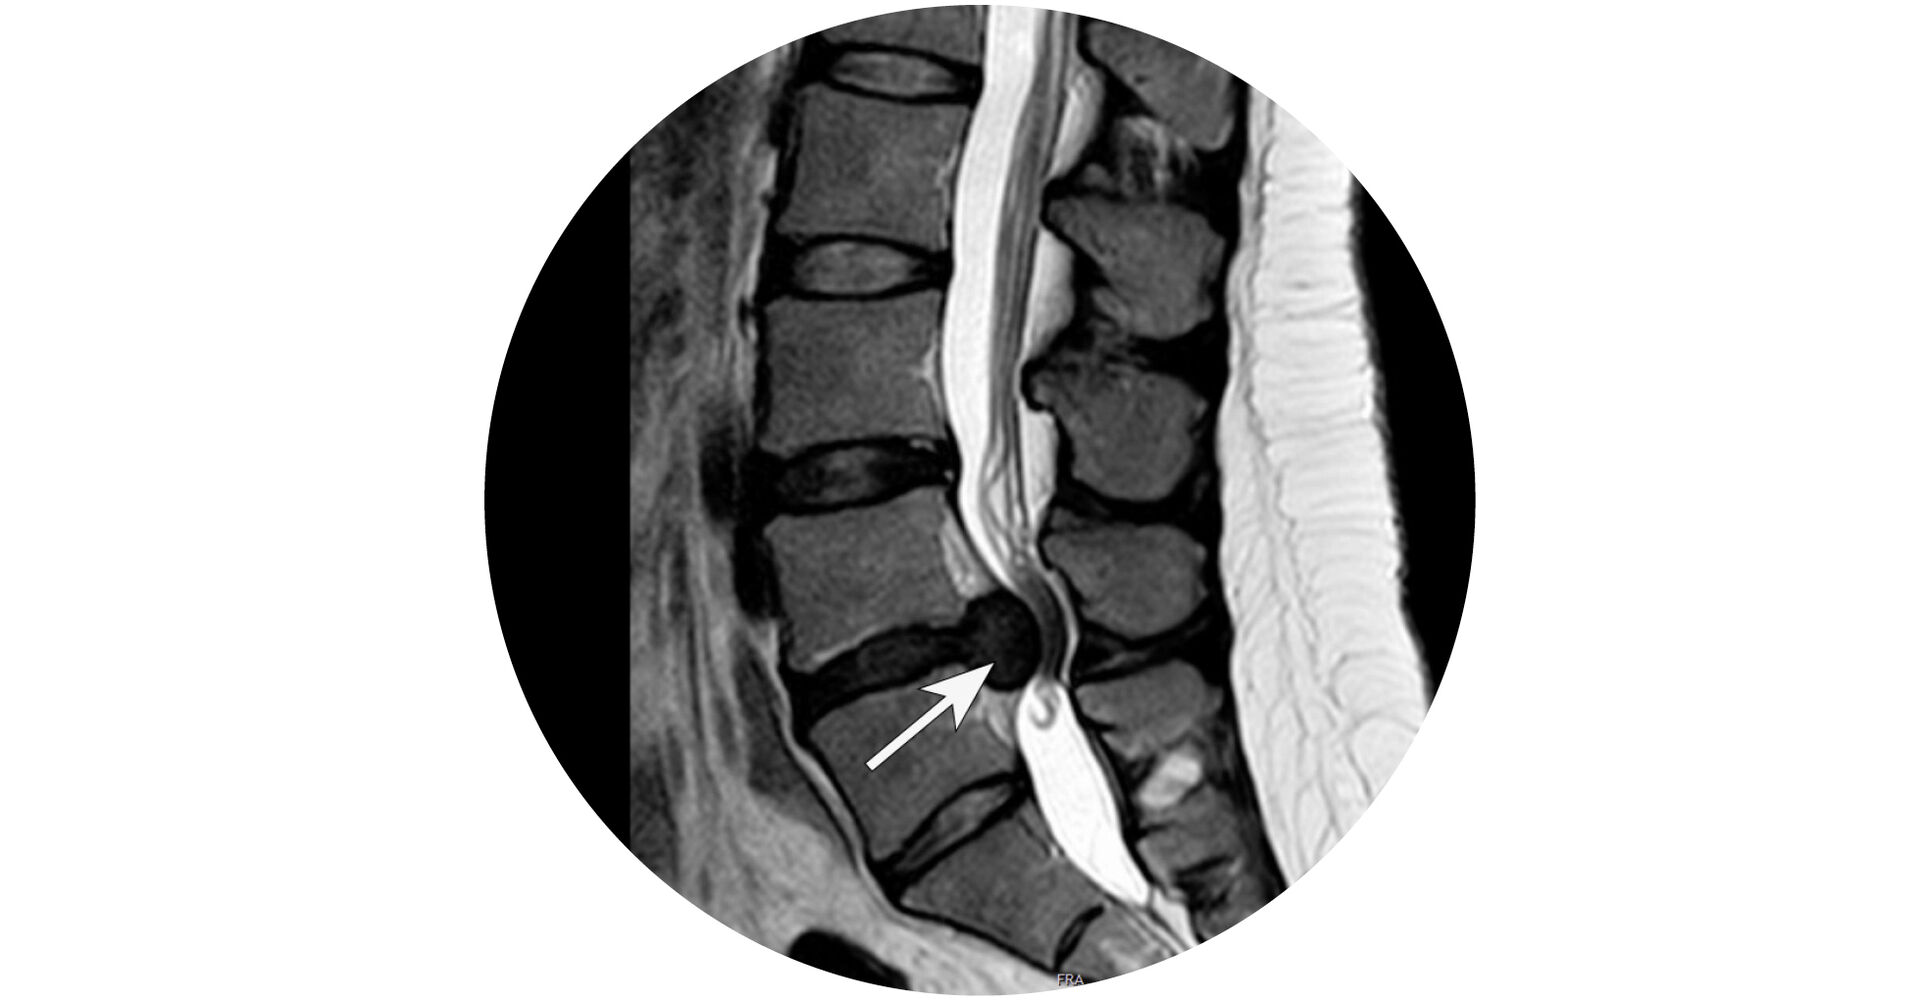

Lendenwirbelsäule

MRT-Aufnahme der Lendenwirbelsäule. Großer Bandscheibenvorfall L4/5 (zwischen 4. und 5. Lendenwirbelkörper) mit absoluter Einengung des Wirbelkanals.